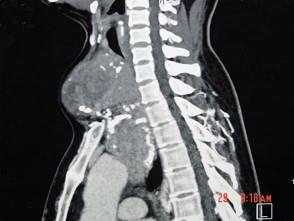

问题 女性,48岁,颈部包块3年,近来胸闷、憋气、胸痛,CT扫描如图,请选择正确的描述和答案 ( )

选项 A、胸骨后甲状腺肿是指甲状腺50%位于胸骨后 B、胸骨后甲状腺肿是指甲状腺60%位于胸骨后 C、考虑为血管瘤 D、考虑为双侧甲状腺肿大 E、考虑为胸骨后甲状腺肿

答案 AE